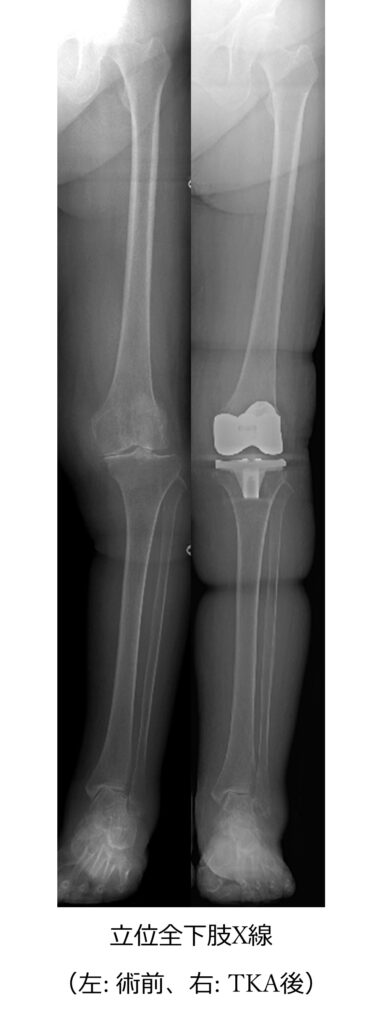

この関係は人工膝関節全置換術(TKA)の術後にも観察されます。TKAによって膝のアライメントが矯正されると、足関節や後足部のアライメントも変化します。多くは正常化の方向へ進み、術前に足関節痛のある方の多くは症状が改善します。しかし、一部の方にはその変化が症状改善につながらず、術後も足関節痛が残る症例があることがわかっています。

このような背景から近年では、膝や足関節の診療において全下肢立位X線によるアライメント評価が重要視されています。股関節から足部までの荷重軸を評価することで、単関節では理解できない病態が見えてくることがあります。 佐賀大学整形外科では、このような運動器の連動性に着目し、膝関節と足関節の相互関係についての研究や診療を行っています。足の痛みを診る際にも足だけを見るのではなく、膝や股関節を含めた下肢全体のアライメントを診ることは、正確な診断と適切な治療につながる重要な考え方です。